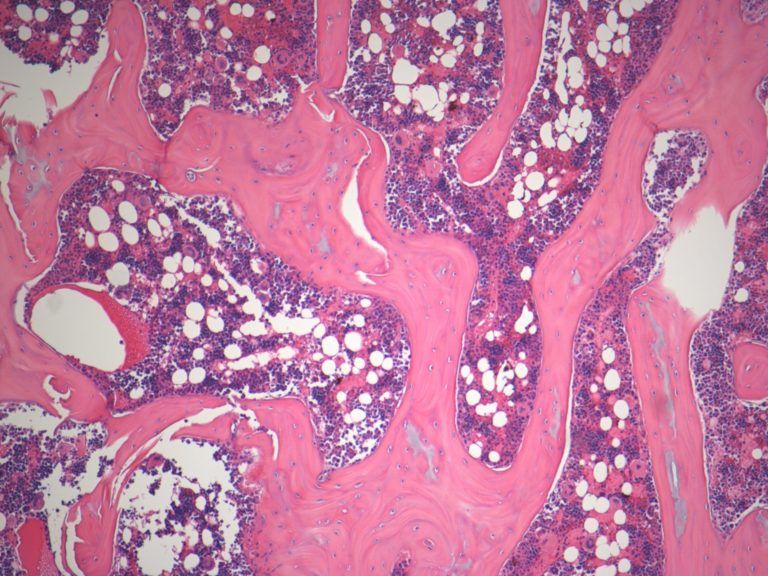

BONE TISSUE EXAMPLES

ADIPOSE TISSUE:

Adipose tissue is fat, a connective tissue that insulates and cushions the body.

It is pretty easy to identify, due to the fact that it looks nothing like most other tissue.

Adipose cells found in my slides:

Same slide with lower magnification.